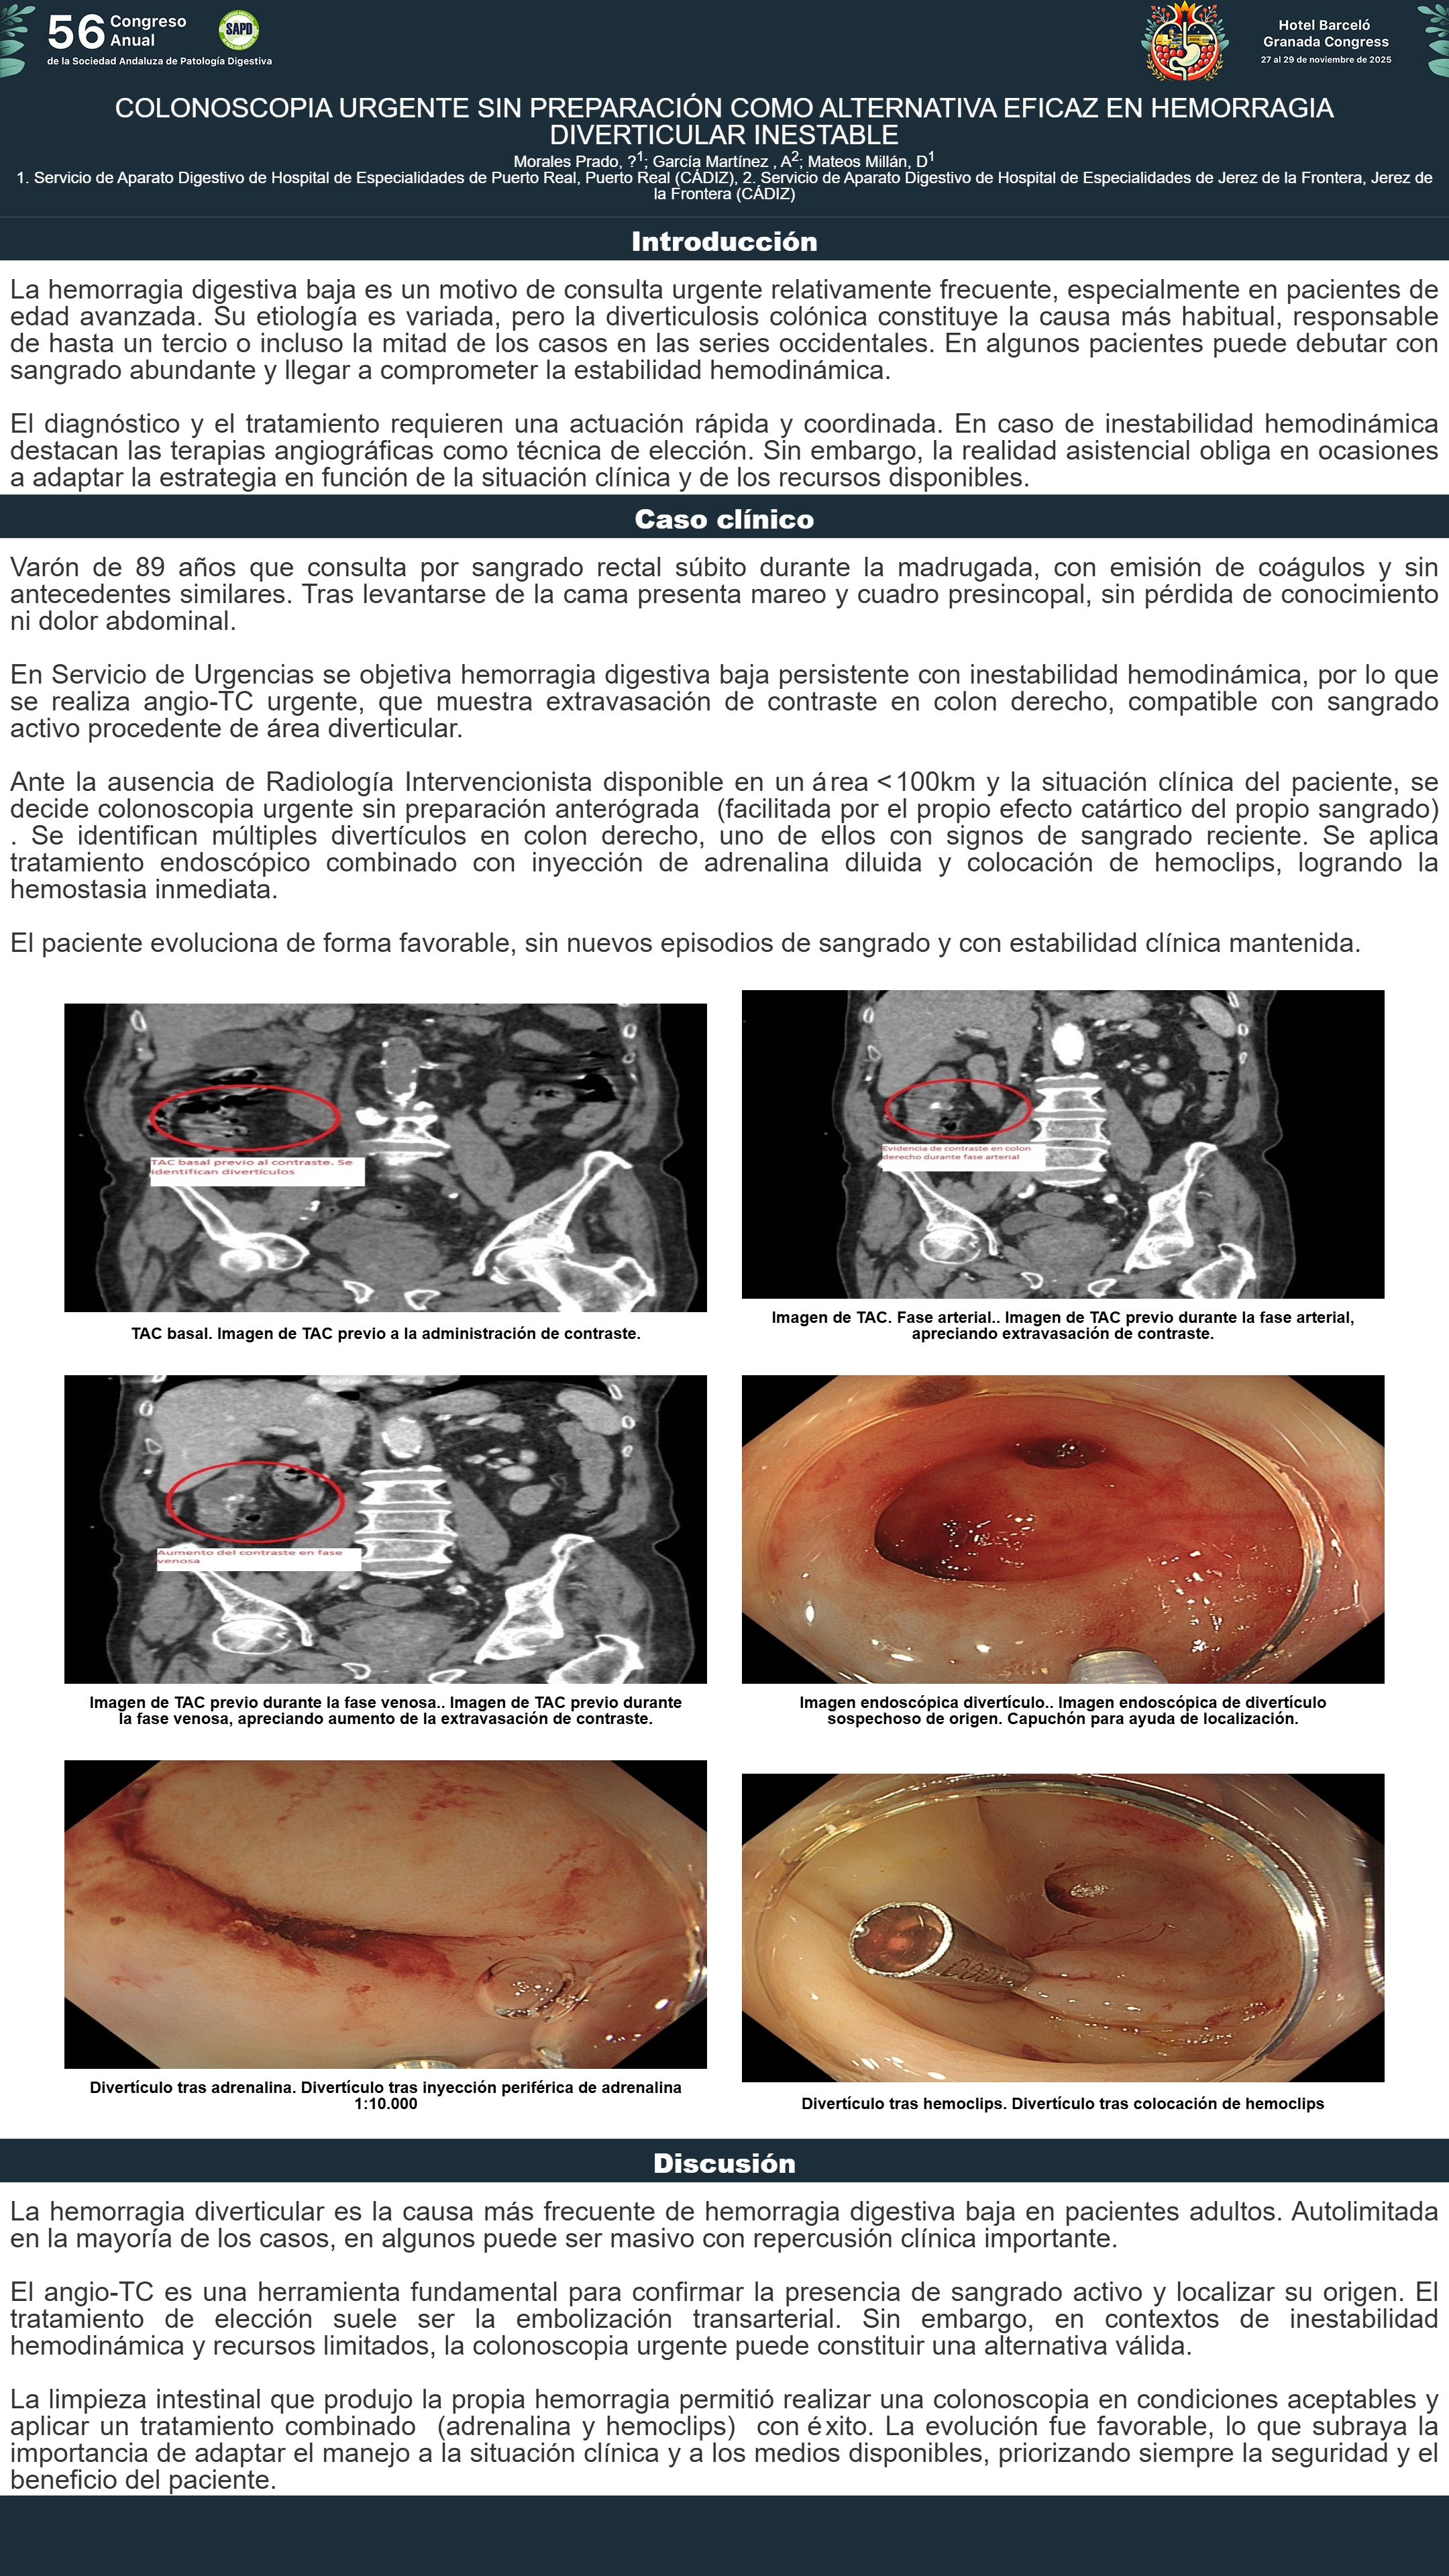

[CP-026] COLONOSCOPIA URGENTE SIN PREPARACIÓN COMO ALTERNATIVA EFICAZ EN HEMORRAGIA DIVERTICULAR INESTABLE